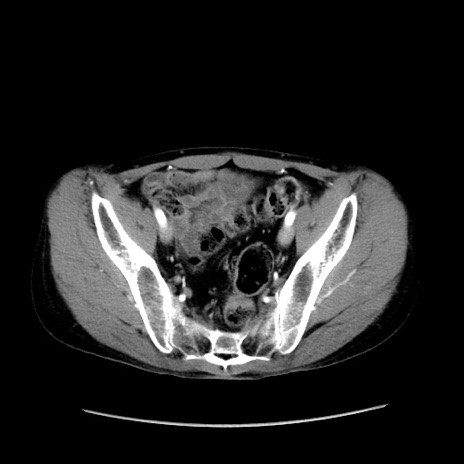

冠状断像